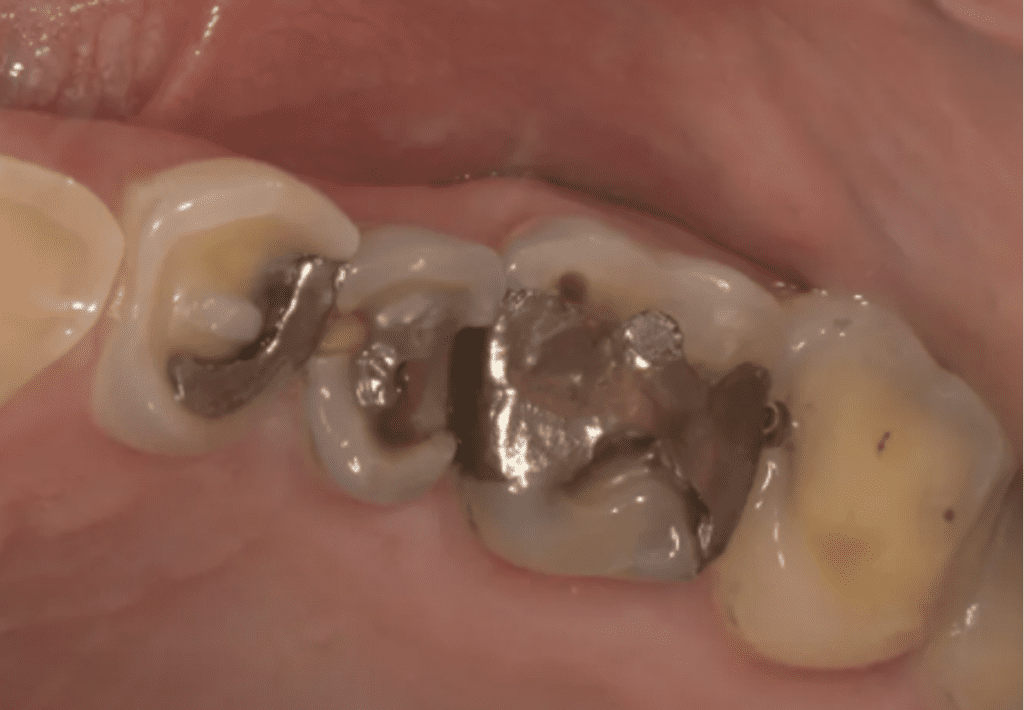

Cuando existe una erosión dental avanzada el esmalte puede desgastarse y descubrir la dentina, las restauraciones pueden comenzar a verse más prominentes si la superficie del diente se disuelve debido a la erosión.

La erosión dental, si no se trata, puede provocar la pérdida progresiva de la superficie del diente. La pérdida de la estructura dental puede requerir un tratamiento dental complejo que incluye restauraciones como carillas, coronas y hasta tratamientos de conducto.